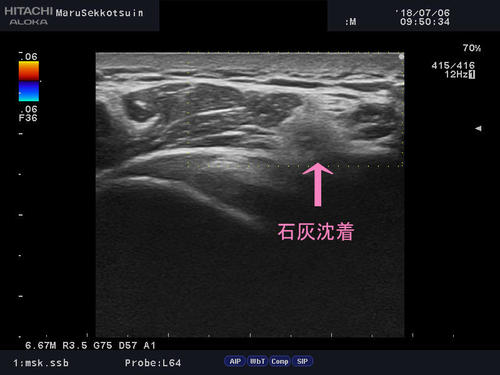

テニスをしていて打ち損ねた後から、肘が痛くなった

石灰沈着2.jpg